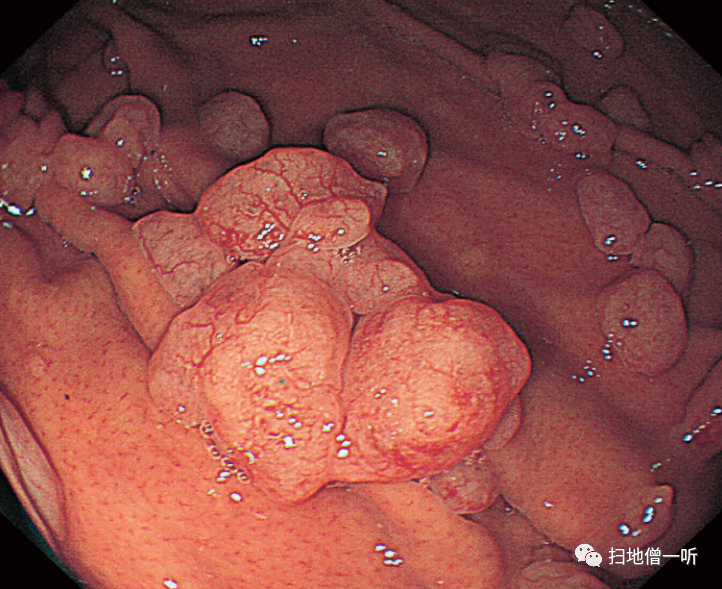

【病例4】

【胃增生性息肉的变化】

患者70多岁,女性。血清抗H.pylori抗体效价(E―plate)为阴性(不足3U/ml)。贲门部的增生性息肉的大小为5mm(红色箭头)。

▼使用PPI/P―CAB 2年后,增大到30mm。附近的红肿息肉也显示了增大的倾向(蓝色箭头),正色调的胃底腺息肉(黄色箭头)没有大的变化。

因使用PPI而发现胃增生性息肉增大的病例。通过投用PPI/P―CAB,贲门部的增生性息肉显著增大,使用Bonoprazan 20mg时,血清胃泌素值为2820 pg/ml,显示出显著的高值。将Bonoprazan变更为雷贝拉唑后,变更后2周内镜检查发现息肉缩小,血清胃泌素值降低到970pg/ml。在病理组织学上,在增生性息肉中发现了小凹上皮的显著增生性变化,但没有异型性。在附近的胃底腺息肉中,在组织学上发现了PCP样所见。